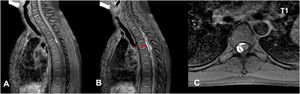

Nervous system involvement is uncommon in granulomatosis with polyangiitis (GPA), a systemic autoimmune disease with episodes of necrotizing vasculitis. It is usually due to the compressive effect of dural or epidural masses. Spinal hemorrhagic presentation is exceptional. A 41-year-old woman diagnosed with GPA presented with three episodes of acute spinal subdural hematoma separated by eight years and ten months, respectively. The symptomatic debut was pain and paresis in all episodes. On all occasions, a lesion compatible with acute spinal subdural hematoma was diagnosed by magnetic resonance imaging (MRI). All episodes were treated conservatively with corticosteroids and immunosuppressants. The patient presented complete neurological recovery in the first two episodes. A mild residual left lower limb paresis remains after the last one. Follow-up MRI was performed after all episodes, and no focal intraspinal lesions were detected. Spinal subdural hemorrhage is a form of manifestation of GPA, either as a debut or in the course of the disease. We describe the third confirmed case of spontaneous spinal hemorrhage secondary to GPA published in the literature and the first with recurrence. Given the extraordinary response to immunosuppressive therapy, a high level of clinical suspicion is necessary to establish treatment as early as possible.

Presentamos un caso en una paciente diagnosticada de granulomatosis con poliangeitis (GPA) que presentó en dos ocasiones separadas por un lapso de 8 años, hematoma subdural agudo espinal con diferentes niveles de afectación en cada uno de los episodios. Se añade una revisión de la literatura. Una mujer de 48 años diagnosticada de GPA, presentó tres episodios de hematoma subdural espinal agudo; separados por un período de tiempo en primer lugar de 8 años y en segundo lugar de 10 meses. Clínicamente, las tres veces se manifestaron con dolor y paresia. En todas las ocasiones, se diagnosticó mediante Resonancia Magnética Nuclear (RMN) la presencia de una lesión compatible con hematoma subdural espinal agudo. Todos los episodios se trataron de forma conservadora con corticoesteroides y Rituximab. La paciente presentó recuperación neurológica completa en los dos primeros episodios. En relación al último; presenta una paresia leve en miembro inferior izquierdo. En todos los episodios se realizó control por RMN y no se detectaron alteraciones intraespinales. La hemorragia subdural espinal es una posible forma de manifestación de la GPA, bien como debut o en el curso de la enfermedad. Es necesario un alto nivel de sospecha clínica para establecer el tratamiento de la forma más precoz posible. Presenta una respuesta extraordinaria a la terapia inmunosupresora. Es posible una recuperación completa a través del tratamiento conservador. Recomendamos un abordaje combinado.